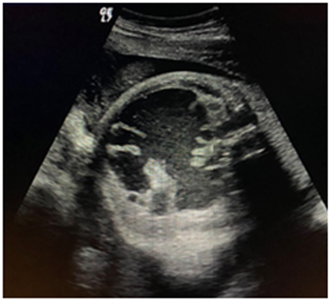

Se realizó seguimiento donde se evidenció que la imagen anteriormente descrita aumentó de tamaño, y se lateralizó a la izquierda del abdomen fetal. Para ese momento, midió 35 mm x 21 mm, ubicada a nivel de asas intestinales ileales (Figura 3). A las 35 semanas, la imagen midió 76 por 75 mm, sacular, hipoecoica, impresionaban haustras intestinales y peristaltismo presente (Figura 4).

Figura 3 23 semanas de gestación, se observa imagen hipoecoica de 35 x 21 mm a nivel de asas intestinales ileales.

Figura 4 35 semanas de gestación, 76 x 75 mm, sacular, hipoecoica, impresionan haustras intestinales y peristaltismo presente.